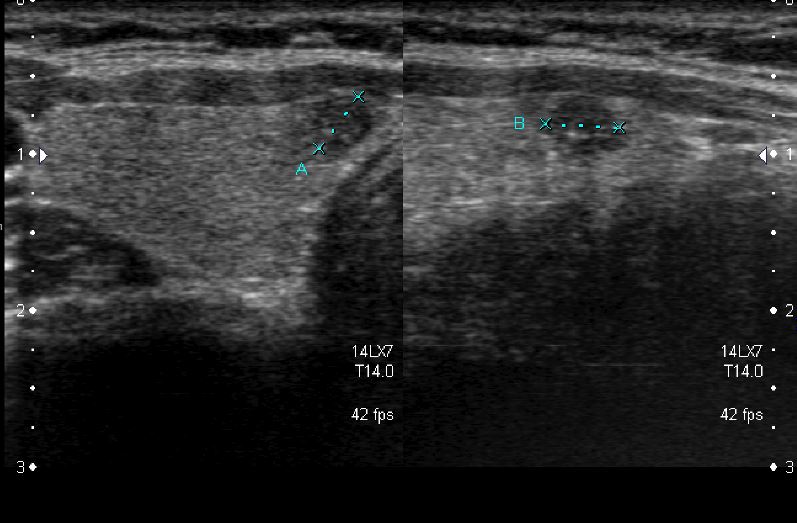

아산유외과 개원후 44번째 갑상선암 진단

상기환자 건강검진상  이상소견으로 내원하신 20대여성분으로 갑상선의 의심스러운 혹

세포검사 시행후 갑상선암 진단되었읍니다.